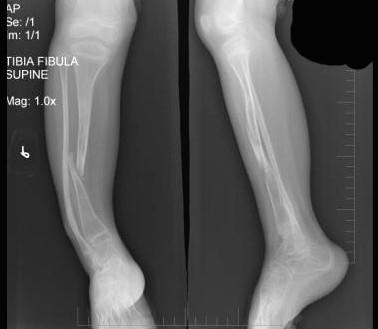

问题 6岁,女性患者,右小腿疼痛,跛行5年,既往无明显外伤史,右小腿正侧位片如图所示,最可能的诊断是 ( )

选项 A、成骨发育不全 B、进行性骨干发育异常 C、先天性骨梅毒 D、先天性假关节形成 E、先天性骨不连

答案 D